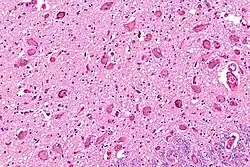

Micrograph showing the locus coeruleus. HE-LFB stain

The locus coeruleus (LC) is located in the posterior area of the rostral pons in the lateral floor of the fourth ventricle. It is composed of mostly medium-size neurons. Melanin granules inside the neurons contribute to its blue colour. Thus, it is also known as the blue nucleus, or the nucleus pigmentosus pontis (heavily pigmented pontine nucleus).[5] The neuromelanin is formed by the polymerization of norepinephrine and is analogous to the black dopamine-based neuromelanin in the substantia nigra.